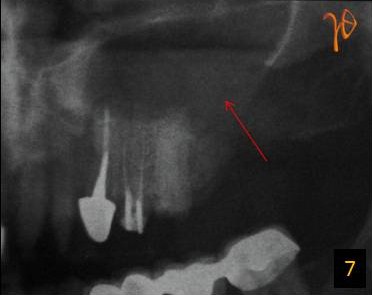

7

Εικ. 7: Πανοραμική ακτινογραφία. Εμφανής η ευρεία στοματοκολπική επικοινωνία (βέλος).

Σε περιπτώσεις στοματοκολπικής επικοινωνίας και ευμεγέθων κύστεων η υπολογιστική τομογραφία μπορεί να συμβάλλει αποφασιστικά στη διάγνωση και το σχέδιο θεραπείας (Εικ.1 – 6). Ωστόσο υπάρχουν και περιπτώσεις ανάλογων νοσολογικών συνθηκών στις οποίες η πανοραμική ακτινογραφία μπορεί να είναι διαγνωστικά επαρκής(Εικ. 7 και 8).